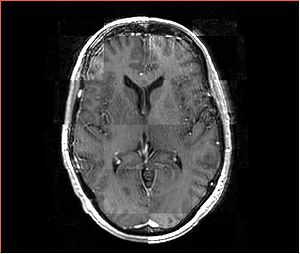

Data

• Input images: isotropic post-contrast T1 MRI acquired at different locations of BWH during 2006-2008, used under medical records study IRB. Time period between acquisition of scans for each patient is about 1 year.

• images were acquired with the same sequence, but possible on different scanners, all scans are axial